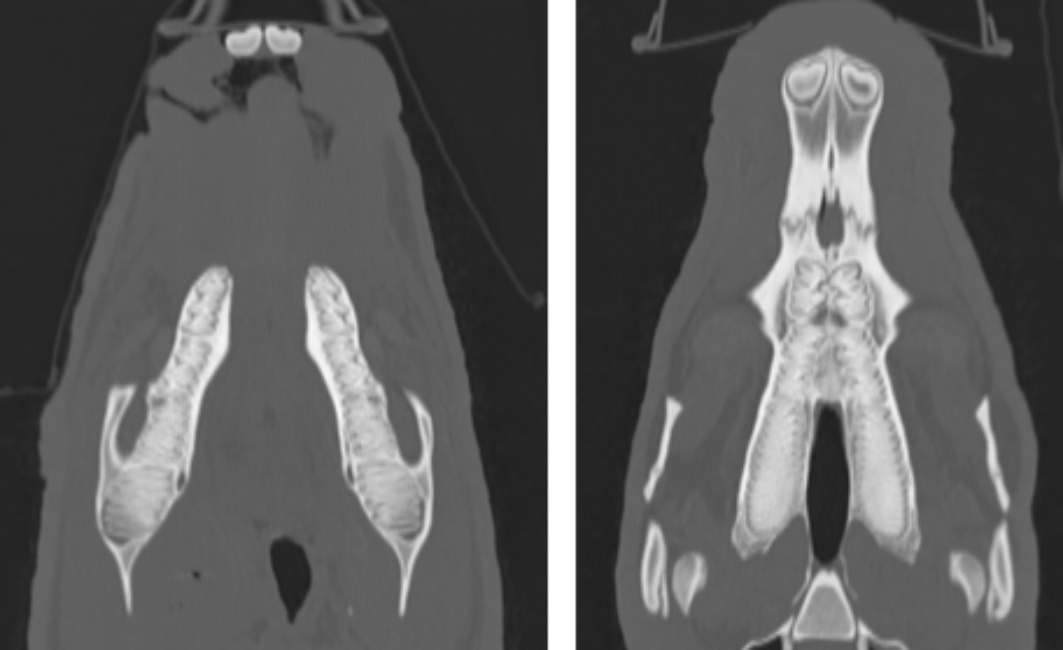

使用万东医疗的OpenCT机,将患病水豚以背卧位及侧卧位保定进行头部平扫和三维成像,影像结果见图1图2

图1(A)可知,其右侧喉咽部会厌水平处有一细棒状金属密度异物影,长度约1.8 cm,周围软组织密度降低,软组织内有多个小气泡影。由图1(B)可知其双侧颞下颌关节未有明显脱位。由图1(C)可知,其右侧鼓室重力侧有层状中等密度影,左侧鼓室内充满气体影,外耳道通畅,耳道壁有点状钙化灶。各牙齿密度正常,齿根处无明显骨质溶解,未有齿根过长,双侧切齿对合良好。脑中线居中,脑实质无明显异常密度影。鼻中隔居中,筛骨完整、对称,鼻腔内无明显渗出影。

Figure 1. CT image of diseased capybara

1. 患病水豚CT影像